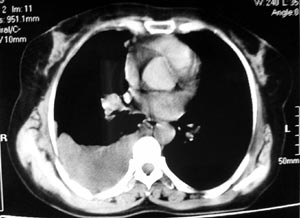

患者女性,52岁,胸闷,咳嗽,活动后气短2个月,加重1周.血常规:wbc10.28,rbc4.62,hgb135,plt267.胸水

常规:李凡他(+).胸水ada:68.1,ldh:303.6.胸水脱落细胞:未查到肿瘤细胞.

右侧肺部感染,胸腔积液,胸膜增厚,不排除肺癌。建议结合病人情况进一步检查。

考虑纵隔旁肺癌伴胸水可能。

同意9楼分析,肺癌,胸膜转移、胸水。

右侧胸膜结节状增厚伴胸腔积液及纵隔、腋窝淋巴结肿大,考虑胸膜间皮瘤可能性大;建议胸膜活检。

右侧中央型肺癌合并阻塞性肺炎及右侧胸膜转移。

右侧肺门淋巴结肿大,伴大量胸腔积液,同侧胸膜结节样增厚,有胸膜粘连,考虑肺癌.